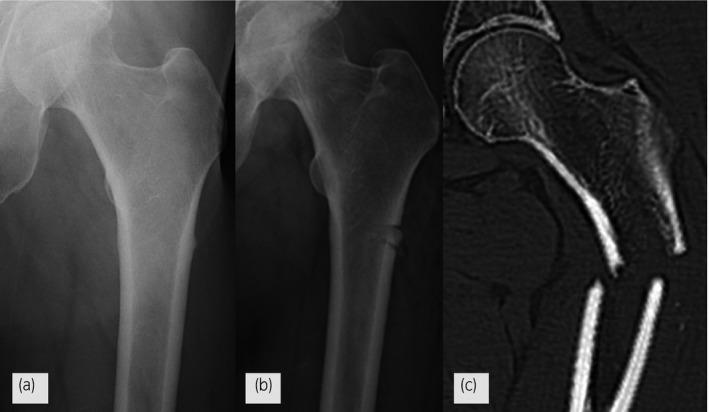

Case of atypical femoral fractures that mimicked the typical imaging findings of prostate cancer-induced bone metastasis.

A 62-year-old man complained of difficulty in walking and left lower limb pain. Androgen deprivation and denosumab therapy for prostate cancer-induced bone metastasis was initiated 27 months ago. Even though the prostate-specific antigen level did not increase, imaging studies indicated the possibility of bone metastasis. The patient underwent bone biopsy; however, no malignancy was detected. Afterward, he had a fall, causing a complete fracture in his left femur.

Atypical femoral fractures occasionally mimic typical imaging findings and outcomes of bone metastasis. This case is important for recognizing such cases.